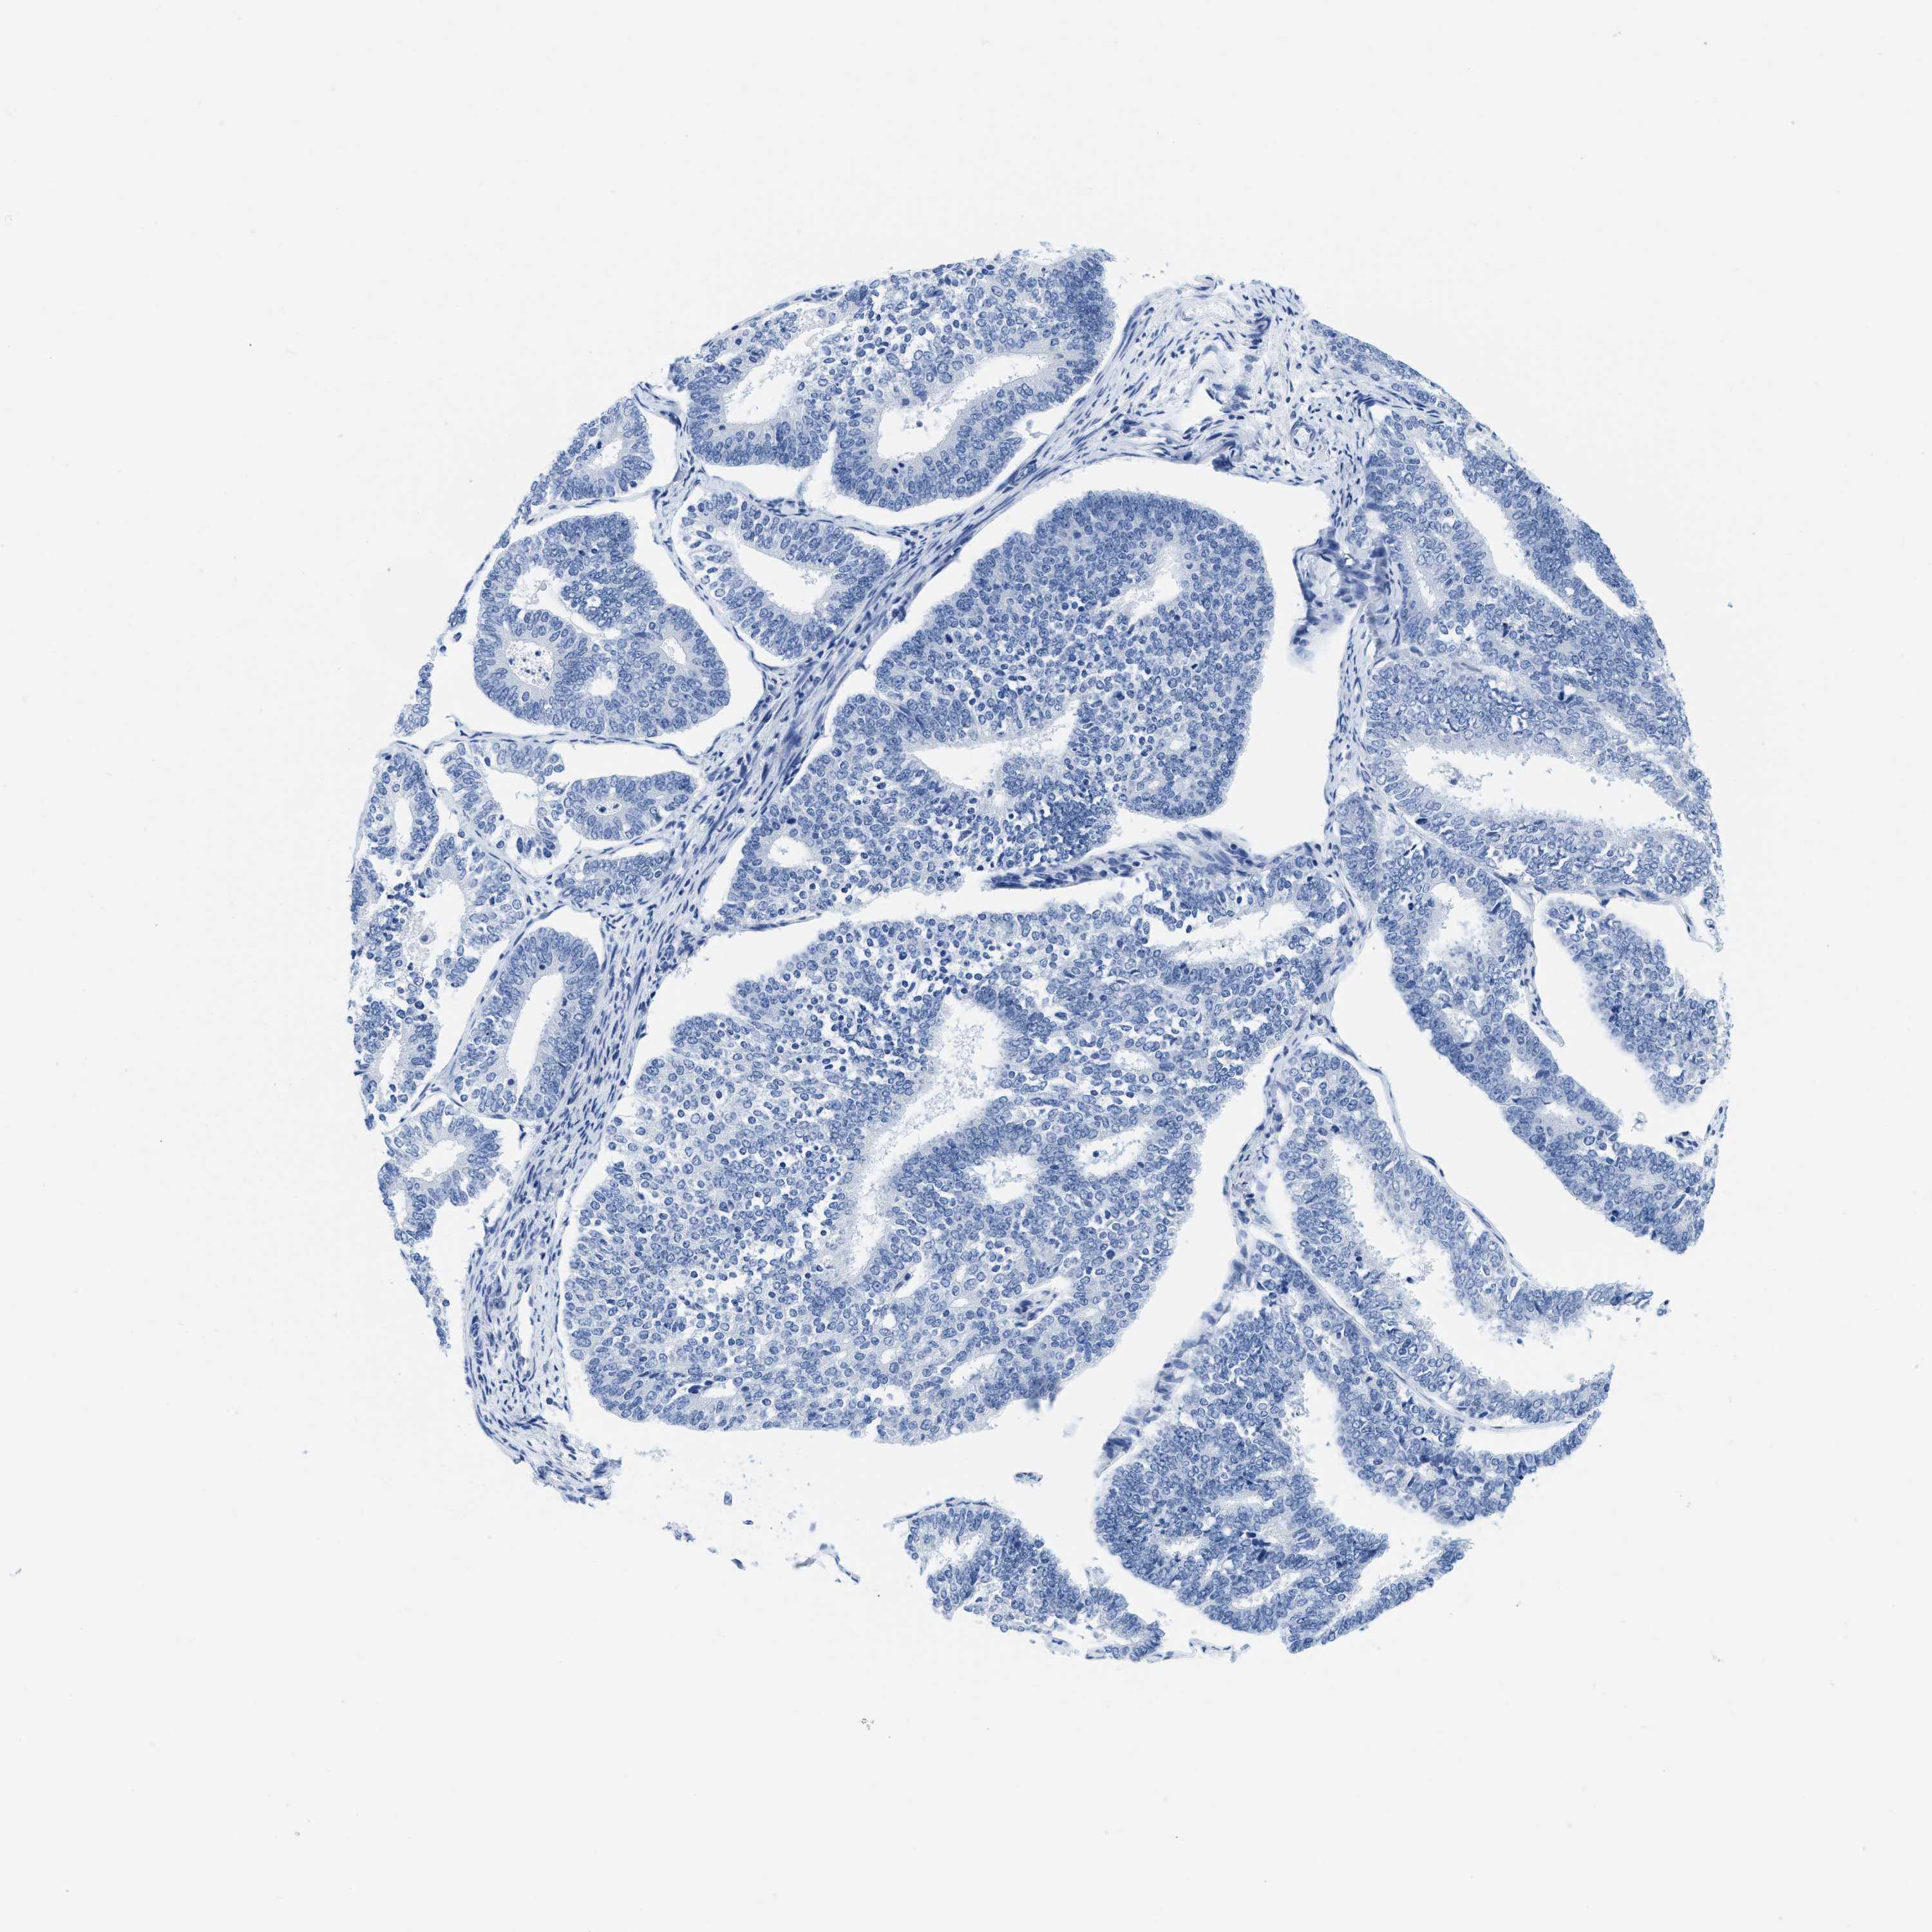

ENDOMETRIAL CANCER - Protein expressioni

A mouse-over function shows sample information and annotation data. Click on an image to view it in a full screen mode. Samples can be filtered based on level of antibody staining by selecting one or several of the following categories: high, medium, low and not detected. The assay and annotation is described here.

Note that samples used for immunohistochemistry by the Human Protein Atlas do not correspond to samples in the TCGA dataset.

Antibody stainingi

Antibody staining in the annotated cell types in the current human tissue is reported as not detected, low, medium, or high, based on conventional immunohistochemistry profiling in selected tissues. This score is based on the combination of the staining intensity and fraction of stained cells.

Each image is clickable and will lead to virtual microscopy that enables deeper exploration of all samples and also displays staining intensity scores, fraction scores and subcellular localization as well as patient and tissue information for each sample.

Antibody HPA054026

Antibody CAB010823

Antibody CAB016728

Antibody CAB036009

Staining

High

Medium

Low

Not detected

Intensity

Strong

Moderate

Weak

Negative

Quantity

>75%

75%-25%

<25%

None

Location

Nuclear

Cytoplasmic/membranous

Cytoplasmic/membranous,nuclear

Adenocarcinoma, NOS

Adenocarcinoma, metastatic, NOS